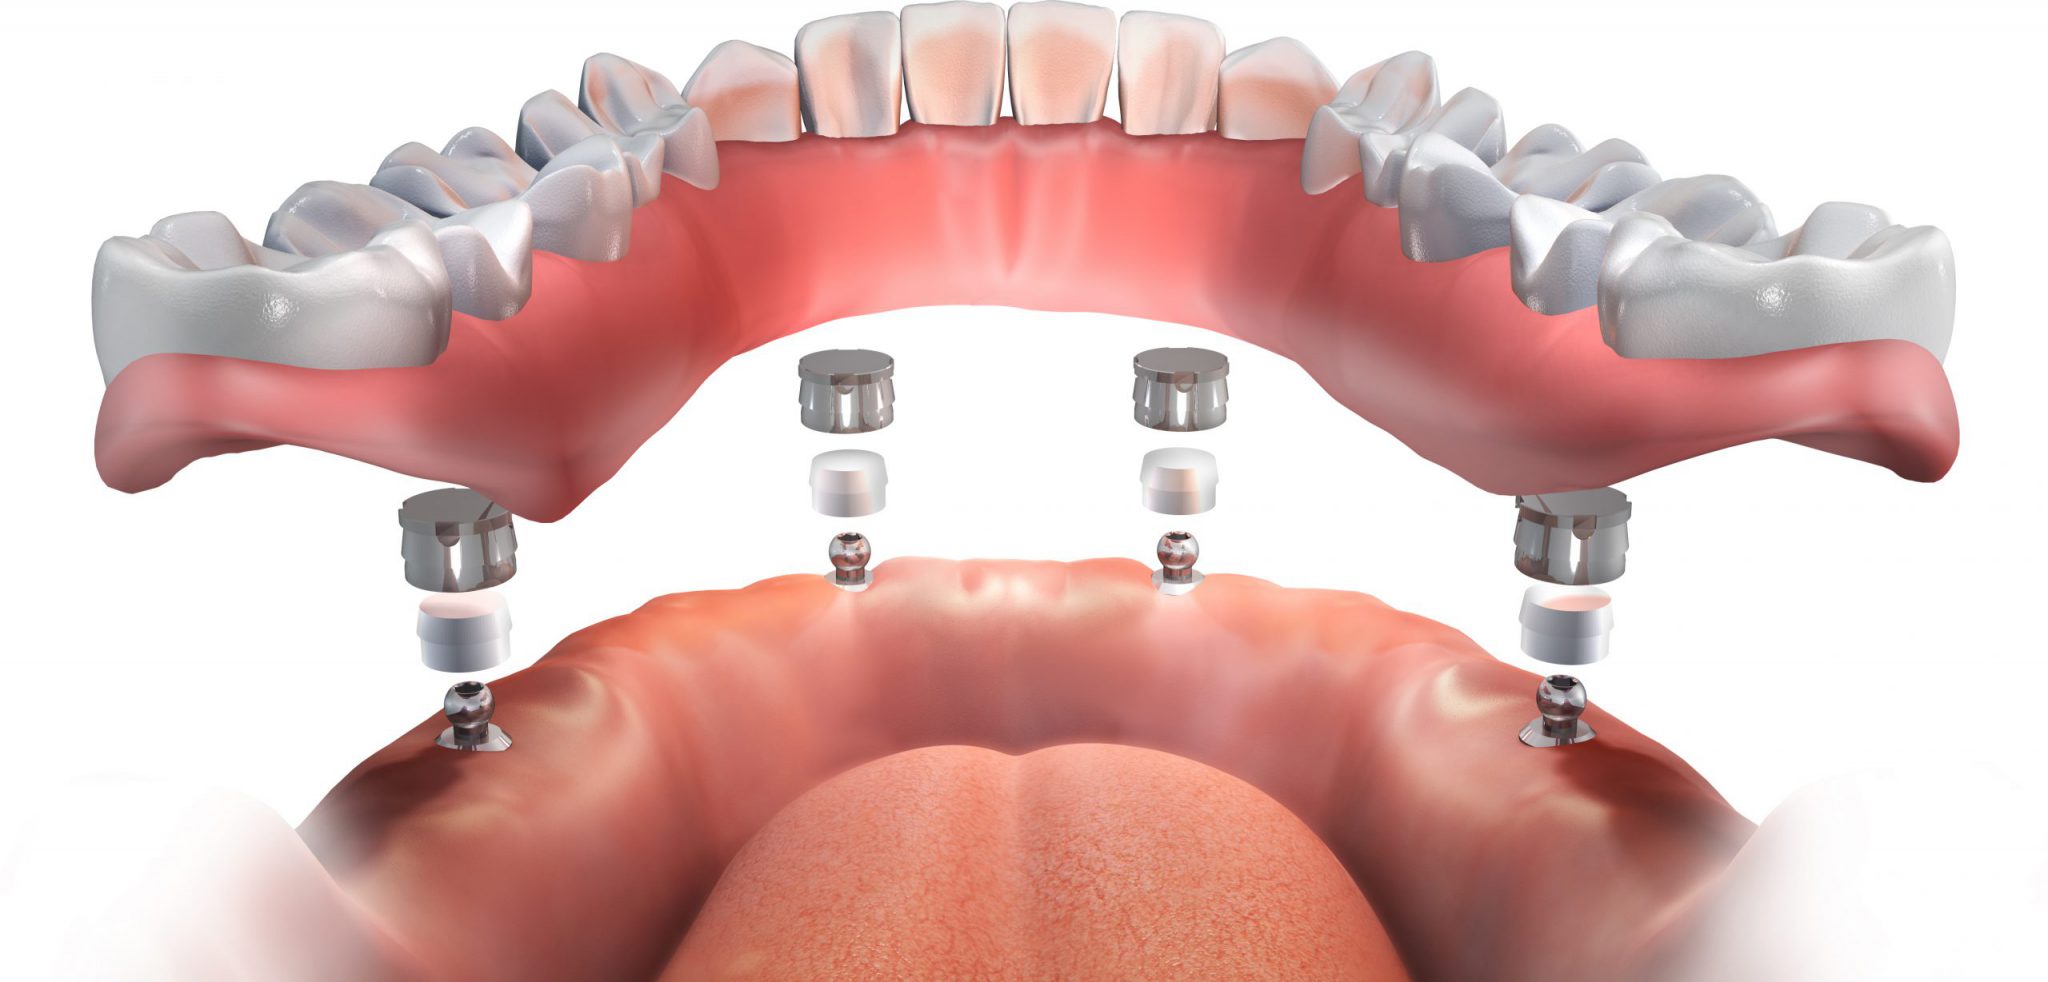

Пошаговое руководство по установке съёмного протеза на импланты